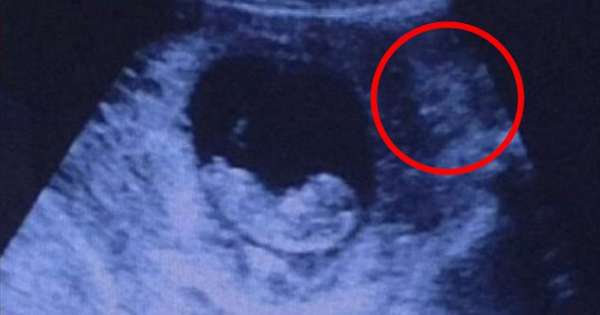

听完上传照片的网友解释后比较心安了。

準妈妈们怀孕后都会定期到医院检查,时刻关注宝宝的健康状况。下面这名準妈妈去医院照超音波,胎儿看起来很健康,但一旁的阴影中却有一个…